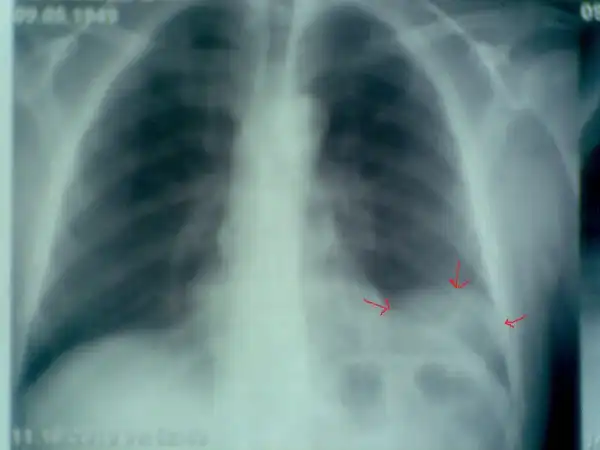

Рак легких в рентгеновском изображении

Пациент № 4: